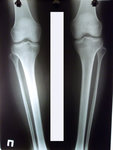

1,5 МЕСЯЦА с момента снятия аппаратов.

Здравствуйте, А.! Сращение железное, ножки в норме. Вы можете ходить на любой вид спорта, фитнеса, каблуки и т.д. Исключить: беременность в первые 6 месяцев с момента снятия аппаратов.